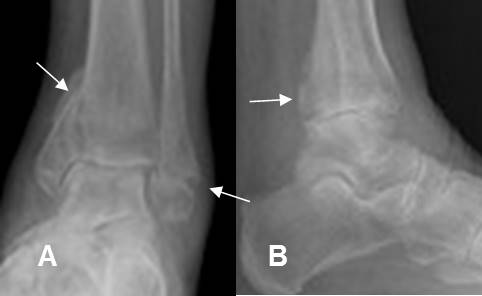

Fig 181. Fractura de Cotton.

A: Rx AP y B: Rx lateral. Fractura trimaleolar, con compromiso de ambos maleolos y la parte posterior de la tibia.

Fig 197. Fractura de Maisonneuve.

A: Rx lateral y B: Rx AP. Fractura espiroidea de la tibia y el peroné proximales, con diastasis de la mortaja tibio-peronea-astragalina, por lesión ligamentaria.